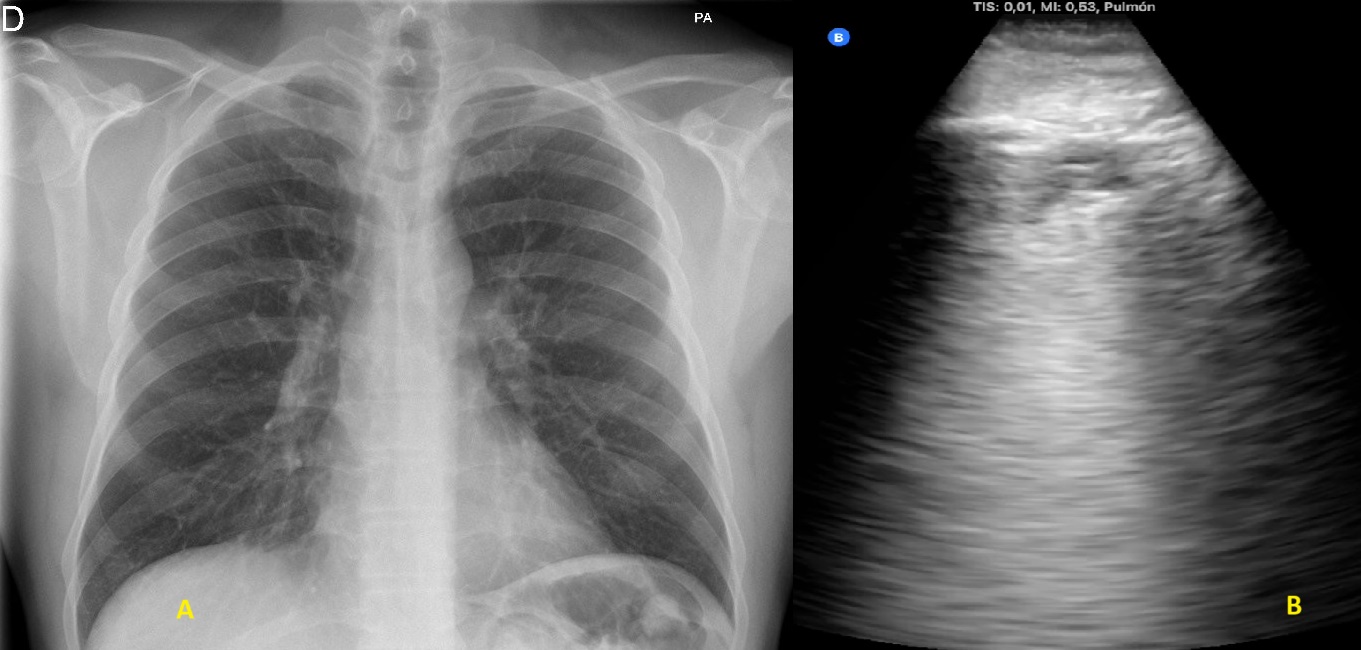

Se hace ecografía pulmonar en ambos casos.

Descripción de los hallazgos ecográficos y las imágenes más relevantes para la resolución del caso

Desaparición de síntomas en los primeros dos días. Seguimiento ecográfico que muestra la desaparición de la neumonía a los 15 días en el primer caso y reducción paulatina del tamaño de la lesión en el segundo.

Se trata de dos casos en los que los hallazgos clínicos y las pruebas complementarias convencionales no hubieran llevado al diagnóstico ni tratamiento adecuados. En el primer caso por una radiografía normal y en el segundo por sintomatología no sospechosa que podría no haber indicado dicha radiografía. La disponibilidad de ecógrafo en la consulta facilita su utilización de inmediato tras la auscultación, detectando las lesiones y consiguiendo una mayor precisión diagnóstica y terapéutica.